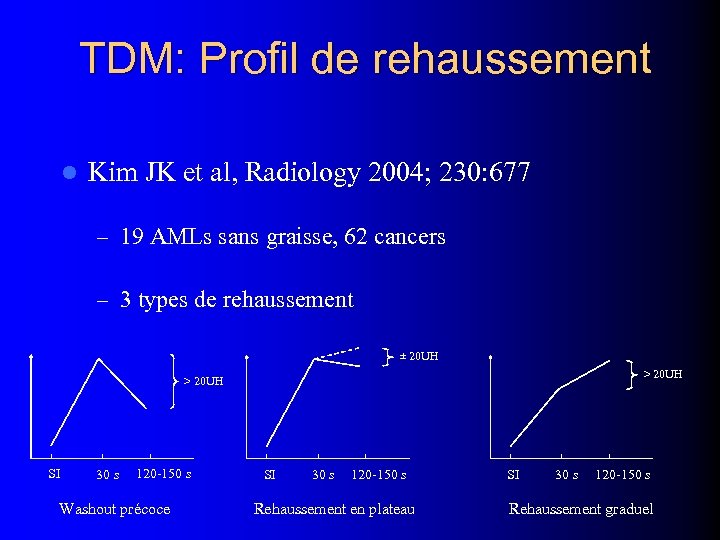

TDM: Profil de rehaussement l Kim JK et al, Radiology 2004; 230: 677 – 19 AMLs sans graisse, 62 cancers – 3 types de rehaussement ± 20 UH > 20 UH SI 30 s 120 -150 s Washout précoce SI 30 s 120 -150 s Rehaussement en plateau SI 30 s 120 -150 s Rehaussement graduel

TDM: Profil de rehaussement l Kim JK et al, Radiology 2004; 230: 677 – 19 AMLs sans graisse, 62 cancers – 3 types de rehaussement ± 20 UH > 20 UH SI 30 s 120 -150 s Washout précoce SI 30 s 120 -150 s Rehaussement en plateau SI 30 s 120 -150 s Rehaussement graduel